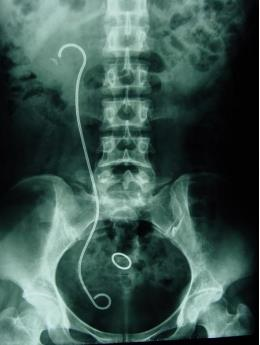

什么是输尿管镜输尿管软镜——微创治疗上尿路结石之“利器”_https://www.jmylbn.com_新闻资讯_第9张

术后双J管 情况